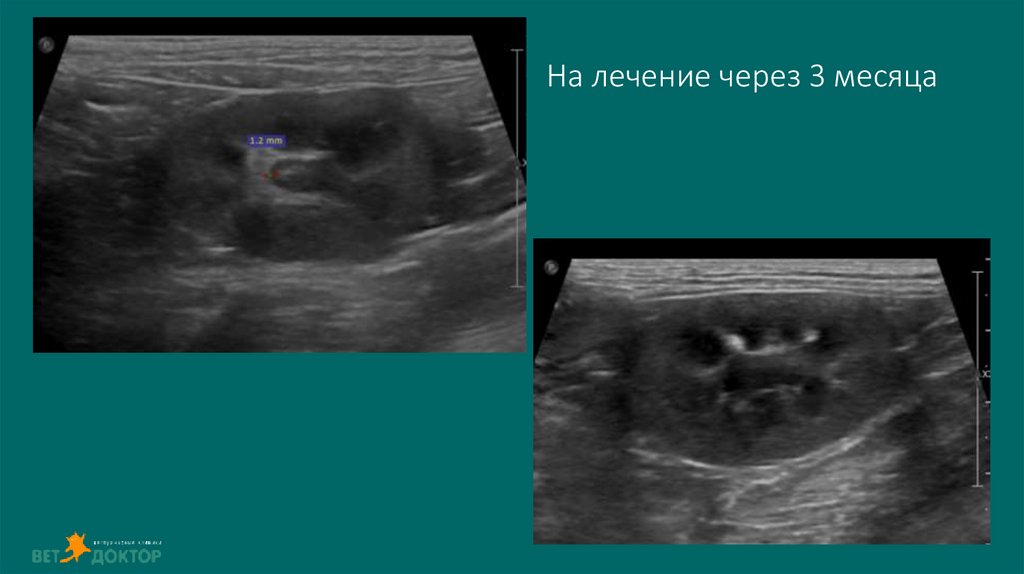

54. На лечение через 3 месяца

55. Видео

На лечение через 3 месяца

Контроль диаметра лоханки(1-2 р/д) и диуреза